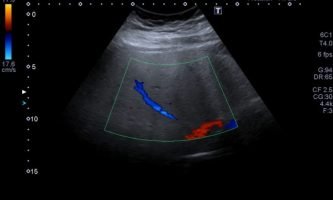

El médico de referencia le indica nueva ecografía de control, donde se observan múltiples y extensas lesiones focales hepáticas hiperecogénicas, redondeadas y confluentes, las cuales predominan en adyacencia a venas supra hepáticas, sin condicionar efecto de masa y sin alteración de la superficie hepática(fig. 1 y 2). Ante la valoración con Doppler color no presenta patrón de flujo peri ni intralesional y respeta el calibre de las venas supra hepáticas(fig. 3 y 4). Dada las características ecográficas se sospecha esteatosis focal multinodular confluente como principal diagnóstico presuntivo, siendo los diagnósticos diferenciales patologías de naturaleza infecciosa, tumoral o metastásica.